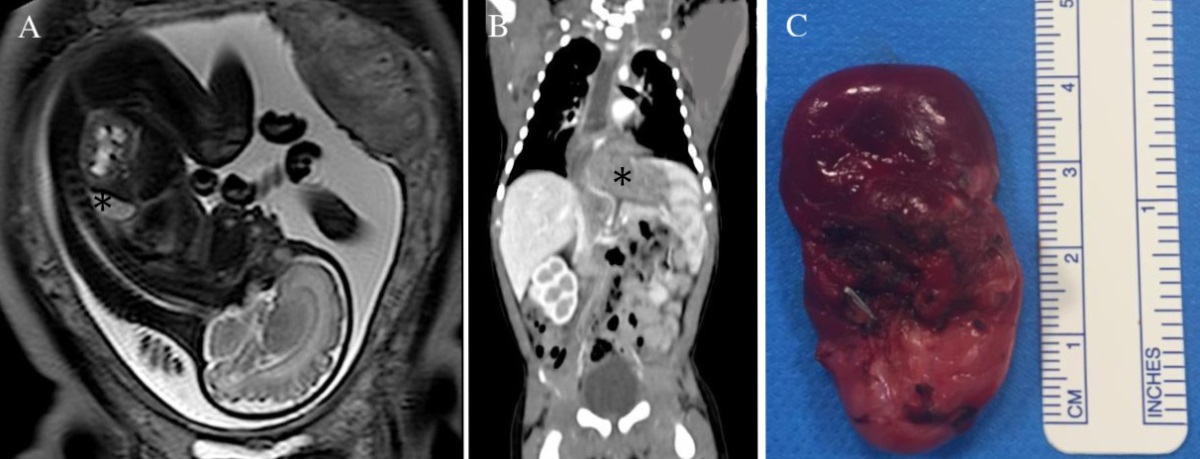

Figure 2

Postnatal computed tomography image showing a triangular-shaped lesion in the lower-left hemithorax, not communicating with the bronchial tree (*). The lesion had an arterial supply from the celiac trunk.

Figure 3

Postnatal computed tomography image showing over inflation in the lower part of the inferior lobe with a solid epi-diaphragmatic mass (*).

A male infant, delivered at term, came to our attention for the prenatal ultrasonography finding of a thoracic mass, suggestive of extralobar pulmonary sequestration. A fetal MRI, performed at 21 weeks of gestation, showed a left-sided lesion (size: 14 x 18 x 15 mm) located in the posterior costo-diaphragmatic recess with an arterial blood supply from the abdominal aorta. The infant was asymptomatic; he underwent a thoracic CT scan at three months to determine the lesion's nature. It confirmed the presence of a triangular-shaped lesion, sized 20x20x17 mm, in the lower-left hemithorax, not communicating with the bronchial tree, with an arterial supply from the celiac trunk and venous drainage towards the hemiazygos system, according to the diagnosis of extra lobar pulmonary sequestration. No diaphragmatic defects were detected (Fig. 2). Surgery was performed at seven months of age via thoracoscopy. At the initial exploration, the mass turned out to slide in thorax from the abdomen through a small Bochdalek's diaphragmatic hernia. Due to the challenge of a thoracoscopic procedure, a left posterolateral thoracotomy was performed, and the lesion was excised "en bloc" with its sac. The diaphragmatic defect was closed with separate non-absorbable stitches. Histological examination confirmed the diagnosis of BPS. Postoperative recovery was uneventful, and the baby was in regular follow-up without any complications.

A male neonate, delivered at term, was referred to our institution for prenatal ultrasonography finding of thoracic mass located in the inferior lobe of the left lung. A fetal MRI, performed at 21 weeks of gestation, showed a hyper-diaphanous area in the inferior lobe with a central area of thickened parenchyma, suggestive of a hybrid malformation mixing congenital lobar overinflation and extra lobar pulmonary sequestration. A systemic vascular supply was not detected. A CT scan, performed at three months of age, confirmed inflation in the lower part of the inferior lobe with a solid epi-diaphragmatic mass. The lesion was 17 x 27 x 15 mm in dimensions supplied by an arterial vessel from the abdominal aorta (Fig. 3). The patient underwent thoracotomy two months later. The inferior lobe was overinflated, and an ELS appeared to come from the abdomen through a defect in the diaphragm. The parenchymal mass was excised, and an inferior lobectomy was performed. The diaphragmatic defect was closed with separate non-absorbable stitches. Histopathological examination confirmed the diagnosis of BPS and lobar emphysema. The postoperative course was uneventful.